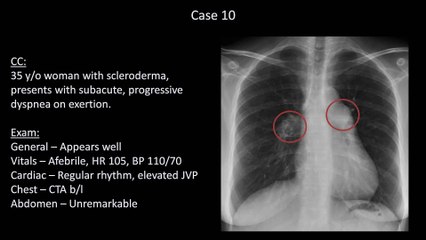

How to Interpret a Chest X-Ray (Lesson 6 - Diaphragm and Pleura)